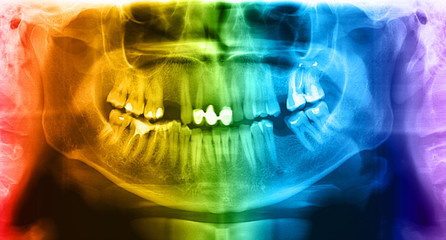

Panoramic radiograph is a panoramic scanning dental X-ray of the upper and lower jaw. This is a focal plane tomography shows the maxilla and mandible of a forty year old man.